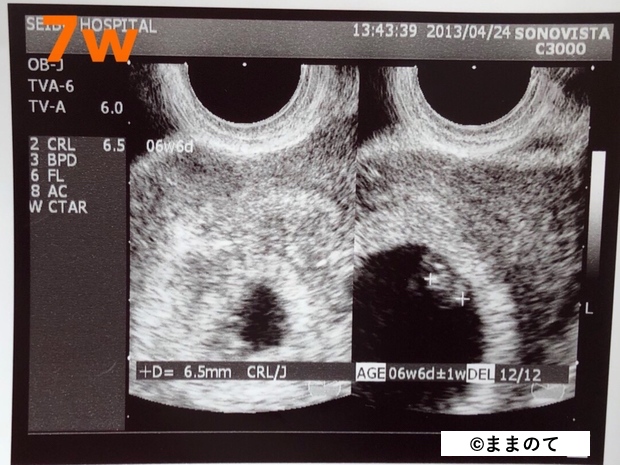

妊娠2ヶ月(4・5・6・7週)

妊娠4~5週にかけて胎嚢が確認できるようになります。目や鼻、口が形成され始めますが、エコー検査ではまだはっきりととらえることはできません。2Dエコーの映像を通じ、心臓が拍動しているのが確認できます。

この時期には身長は2~3cm、体重は約4gほどになります。大人の親指やそら豆ほどの大きさです。

上の画像は、双子の赤ちゃんの妊娠7週のエコー写真です。